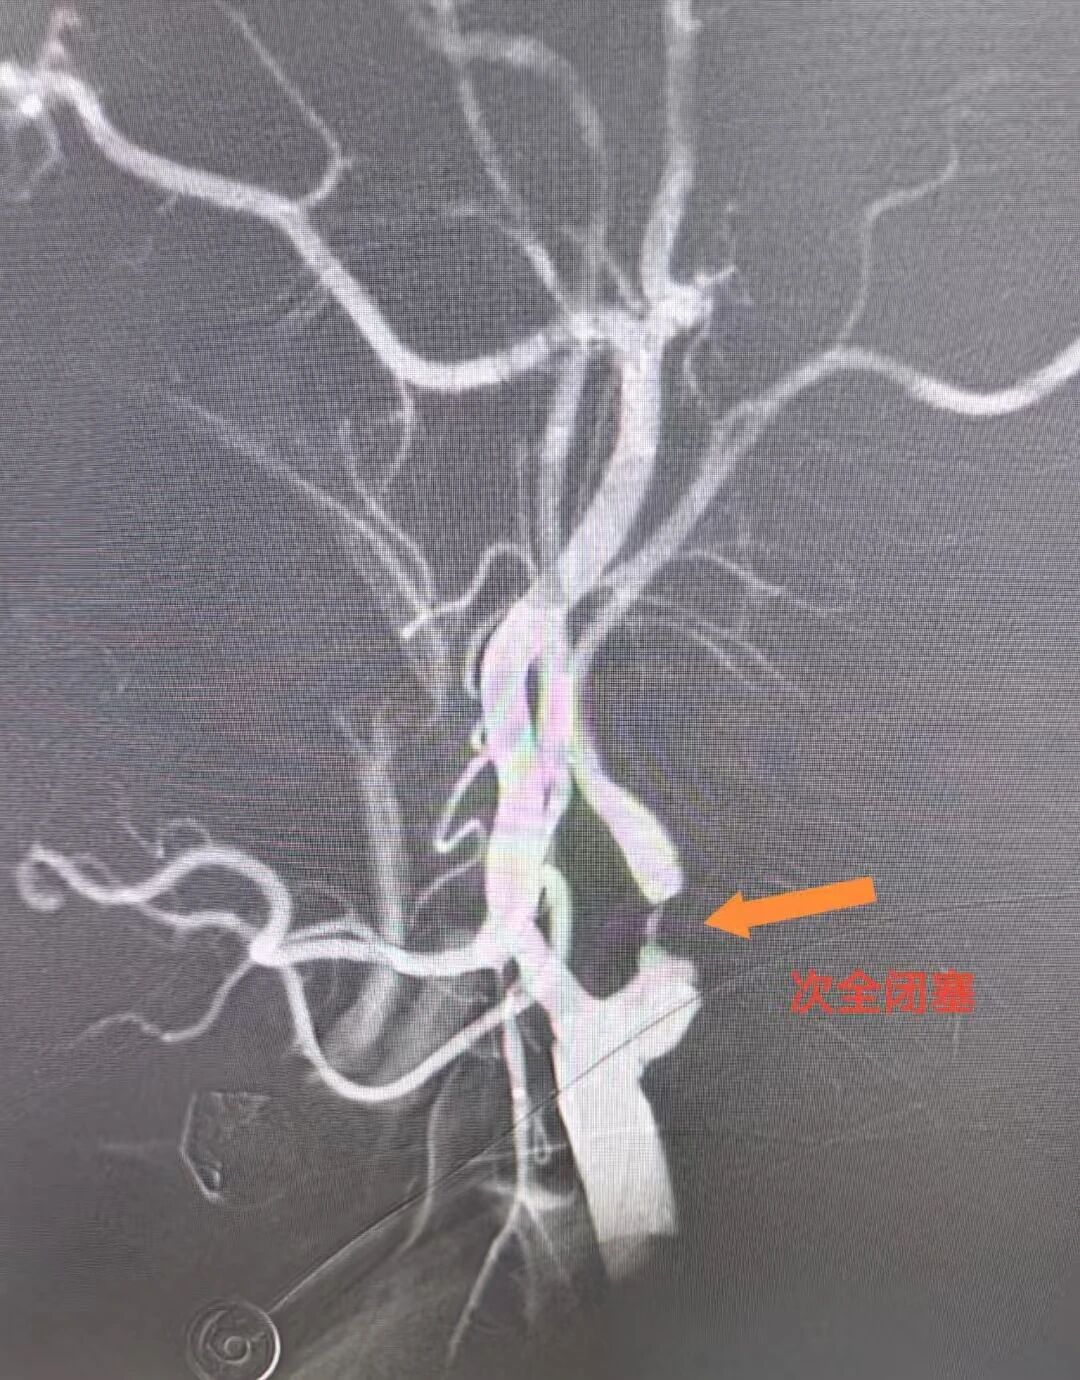

心脏问题刚解决,脑部危机便接踵而至。医疗团队迅速为罗先生实施脑动脉造影,结果显示其右侧颈内动脉近段狭窄达99%。然而心脏术后需维持稍高血压保障心功能,颈动脉支架手术却要求严控血压以规避脑出血风险——两种治疗需求如同天平的两端,在罗先生体内形成了棘手的治疗矛盾。手术团队经过反复研讨、全面评估,与家属进行了充分沟通,决定暂缓脑部手术,给予患者充分的恢复时间,待身体条件达到最佳状态后,再实施颈动脉支架植入手术。

DSA显示罗先生颈动脉闭塞